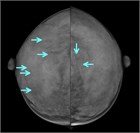

1. 30~40歳代の成熟期女性に好発する、硬結・腫瘤、疼痛、乳頭異常分泌などの症状を呈する乳腺の良性疾患である。